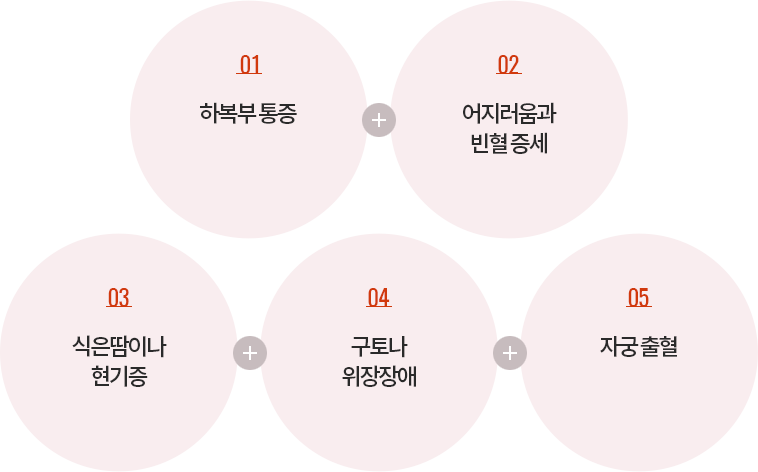

중절수술 후 회복과정에서 나타나는 증상

Pregnancy symptoms

중절수술을 하게 되면 유산 당일 수술 직후부터 생리통과 같은 아랫배 통증이 있을 수 있습니다.

진통제를 사용하게 되면 도움이 되지만 수술 직후에는 과다 자궁출혈을 예방하기 위해 자궁수축제를 사용함으로써

통증이 심한 경우도 있으므로 하복부의 통증이 오히려 자궁수축에 도움이 되기도 합니다.

자궁수축과 관련되어 아랫배의 통증이 너무 심할 경우에는 자궁의 근육이 과도하게 수축되는 것을 풀어주고

적절한 자궁근육 이완을 도와주는 보조적인 치료가 필요하기도 합니다.

어지러움과 빈혈 증세를 느끼고 식은땀이나 현기증을 느끼기도 합니다.

심한 경우 구토나 위장장애가 동반되기도 합니다.

중절수술 이후 일정기간은 출혈이 보이는데요.

출혈은 수술을 받을 당시의 임신 주수에 따라 1주~ 3주 가까이 자궁 출혈이 지속되기도 합니다.

임신중절수술은 순조롭게 진행되던 임신의 과정에 여러 가지 이유로 도중에 갑작스럽게 중단되는 상황이라서

수술 이후 충분한 회복을 위한 안정 및 염증치료가 매우 중요합니다.